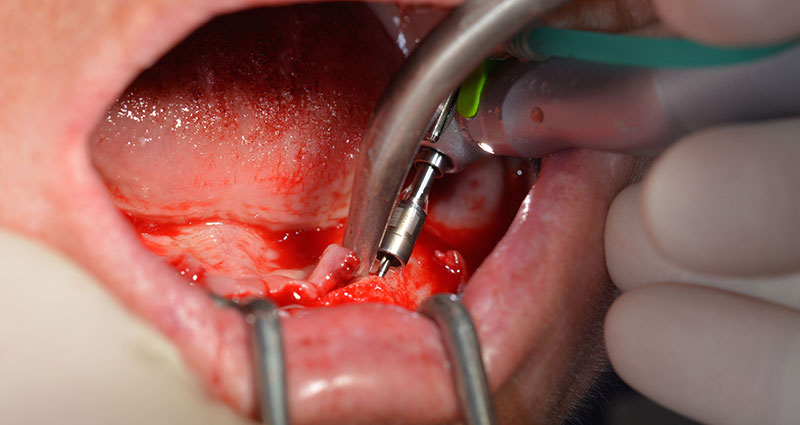

След отстраняване на частичното обеззъбяване в долната челюст, алвеоларният гребен е разкрит от 37 до 47.

Изходът на долночелюстния нерв е първоначално идентифициран като ограничена анатомична структура и, след това, кортикалната кост на гребена е загладена с прав наконечник и голям борер с розовиден профил (Фиг. 4).